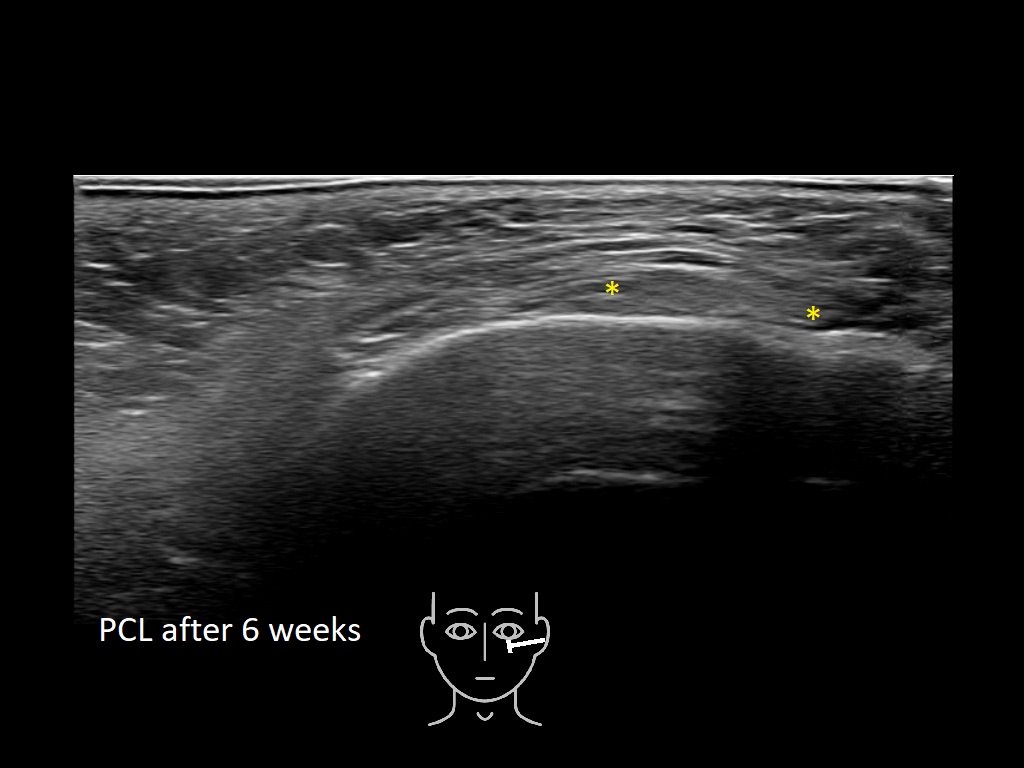

Draw in the image on the right where the fillers are located. To check if your answer is correct, please click on the secondary image.

Fillers